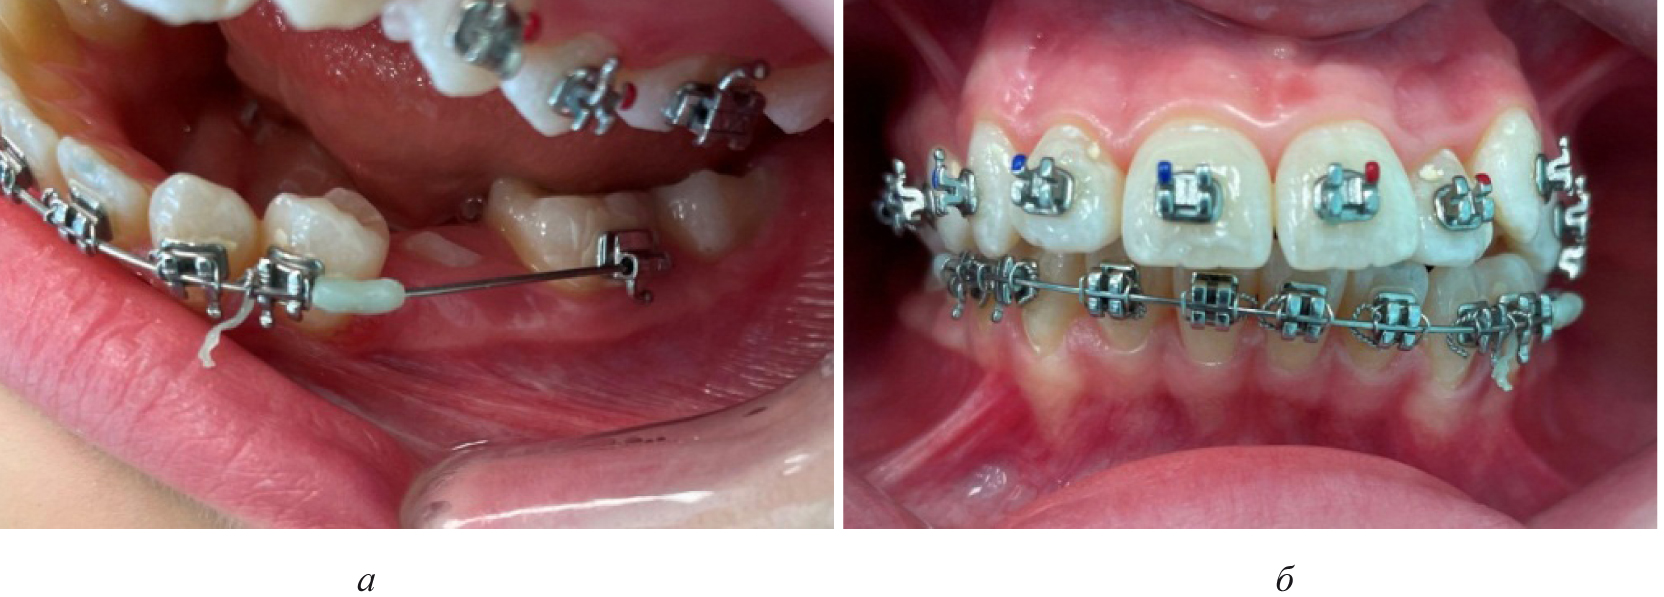

Положение клыков и моляров оценивали по расположению ориентиров (рвущий бугор клыка и дистальный одонтомер вестибулярной поверхности моляра) относительно условной сагиттали. Измерения проводили по сагиттали, диагонали и трансверсали и сравнивали с расчетными показателями индивидуальной нормы (рис. 1).

Рис. 1. Гипсовая модель со смещением резцового ориентира (а) и состояние полости рта с ретенцией второго премоляра (б)